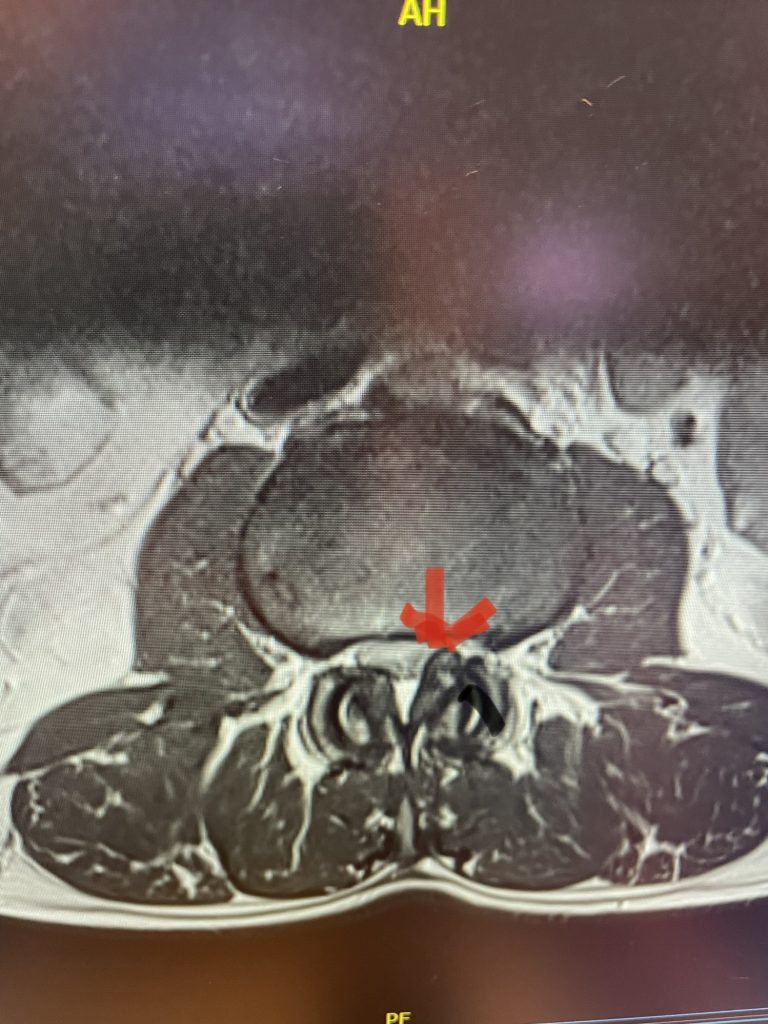

The spinal synovial cyst is one of the most interesting expressions of spinal instability. They emanate from the synovial lining of a degenerated facet joint that […]

The actual structural cause of lumbar thecal sac compression can vary in degenerative spondylolisthesis and stenosis. The culprits are commonly thickened ligamentum flavum or severe facet […]

People are obsessed with cysts! When you think about it, the body likes to form cysts. Why does this happen? Cysts can form just about anywhere […]